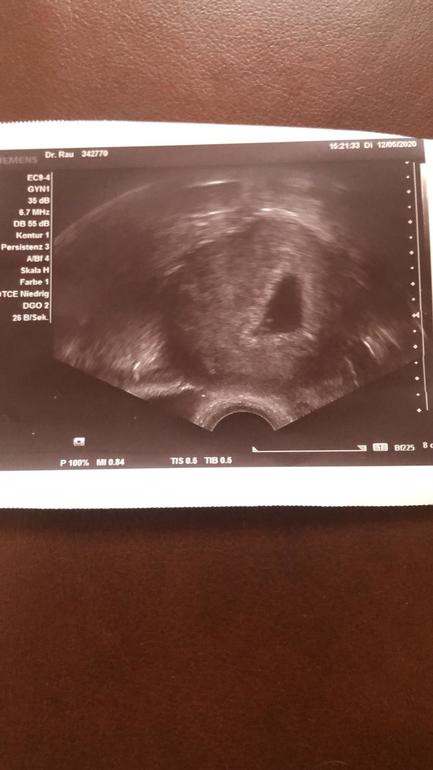

У меня вот так было, вообще ничего не понятно🤷🏻♀️